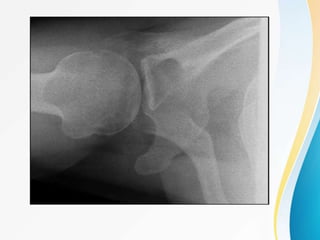

• Radiographs :- consist of three views :

• AP- Perpendicular to the plane of scapula(Grashey view)

Taken in neutral arm rotation with torso rotated 30 to 45

degrees